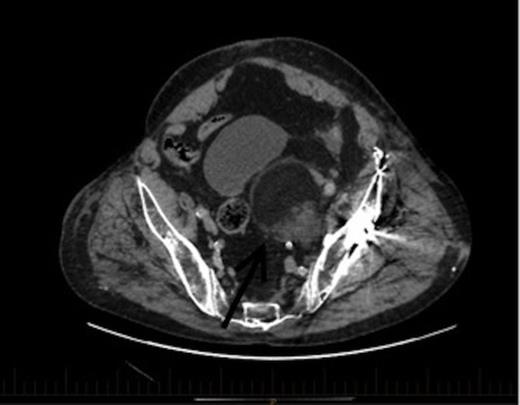

An axial section of the CT demonstrating a 6.7x6cm.3x7.3cm left pelvic lesion adjacent to the trauma site. Arrow denotes the EMH lesion

A CT scan demonstrated a 6.7x6.3cmx7.3cm well-defined left pelvic mass immediately medial and adjacent to the left acetabulum compressing the bladder and the iliac vessels. The mass was heterogeneous in density comprising of both muscle and fat with no calcifications. He underwent a repeat staging-CT, MRI, whole body thallium scan, and a CT-guided biopsy. The MRI scan confirmed a lobulated well-circumscribed mass with a heterogeneous T1 and T2 appearance. Areas of hyperintensity reported on CT corresponded to fatty components within the mass, while the rest of the mass appeared relatively hypointense to skeletal muscle, and was thought to be consistent with a liposarcoma. The Single Photon Emission Computed Tomography (SPECT) scan demonstrated low-grade activity in the mass and the staging-CT did not reveal any signs of malignancy. A confirmatory CT-guided biopsy however diagnosed the mass as EMH tissue, while a CT angiogram demonstrated no external compression of the iliac vessels.